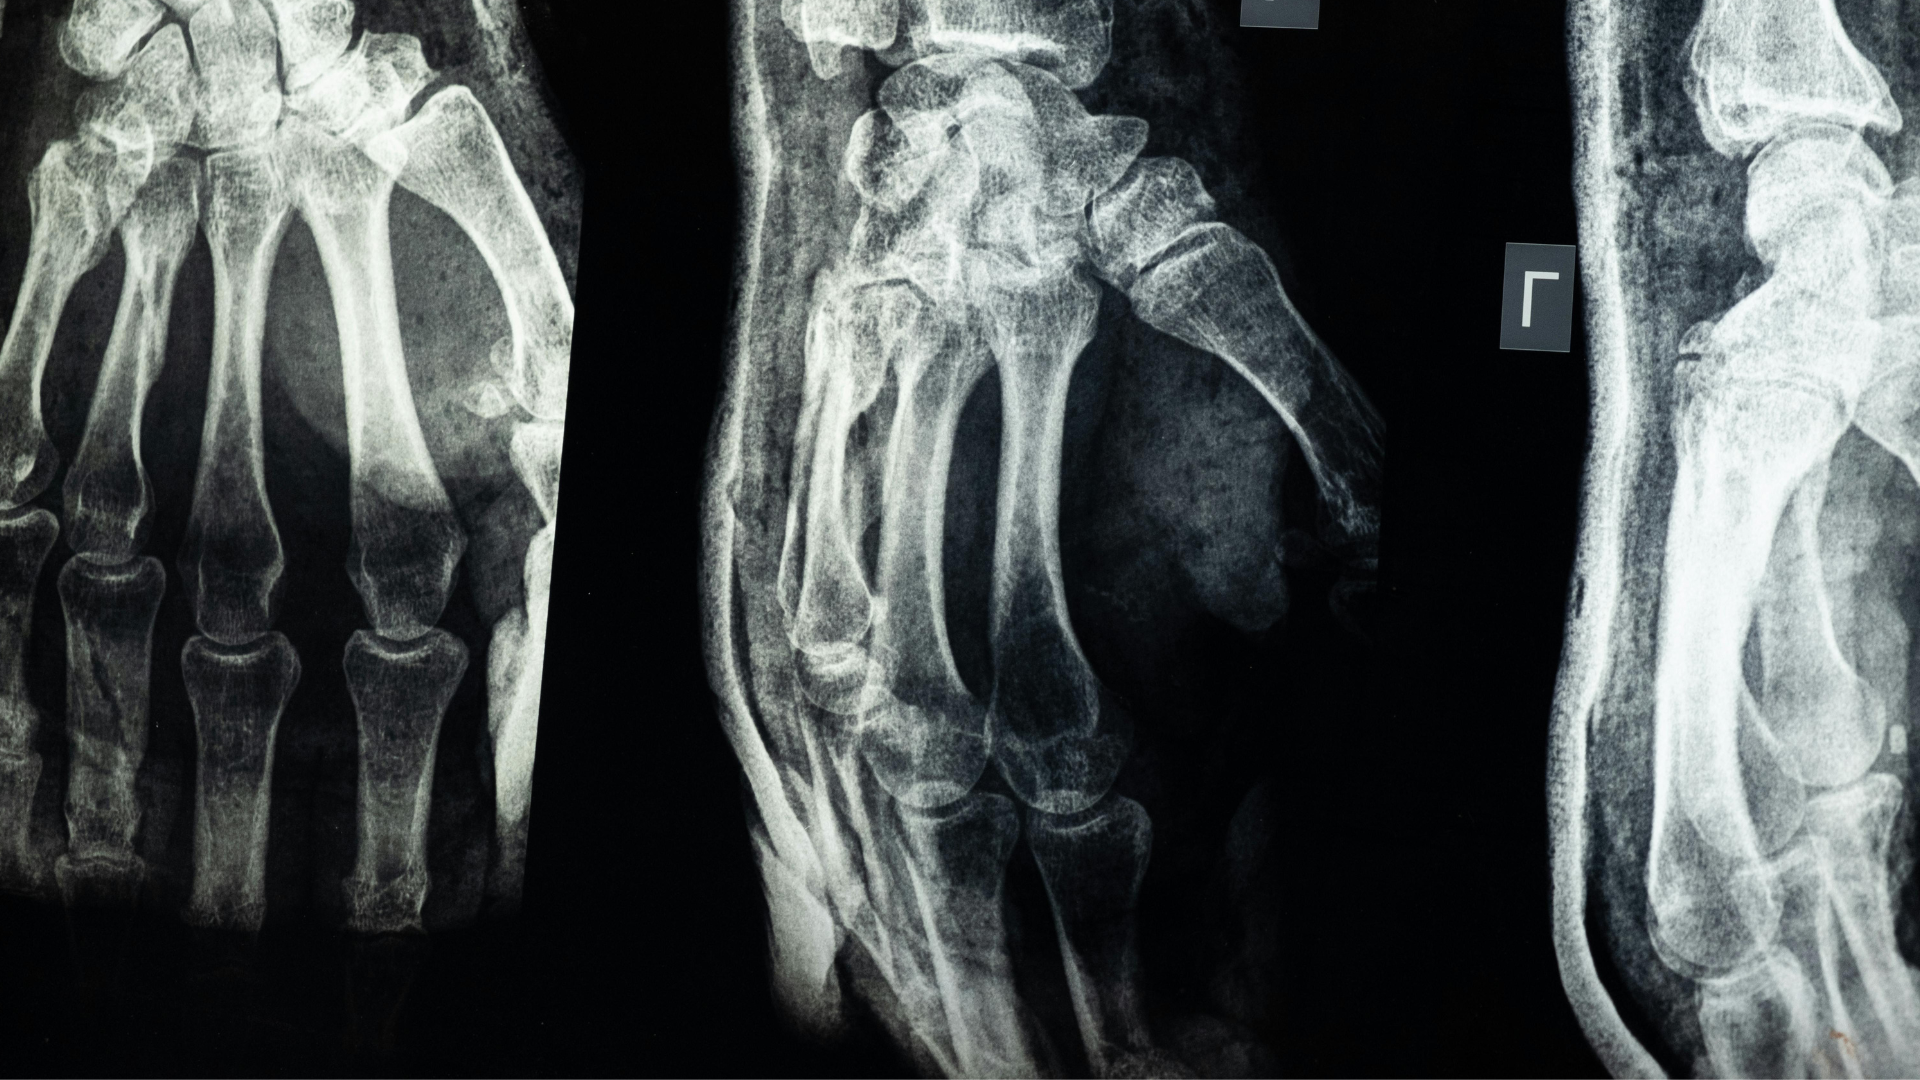

How Are Hand and Finger Fractures Diagnosed?

hand & finger fracture diagnosis boise

At Idaho Hand Center, diagnosis begins with a physical examination to assess swelling, alignment, and mobility. We often use X-rays to confirm the location and severity of the fracture. In complex cases, CT scans may be used for more detailed imaging.

Early and accurate diagnosis is essential; delays in treatment can lead to improper healing, stiffness, or arthritis in the affected joint.